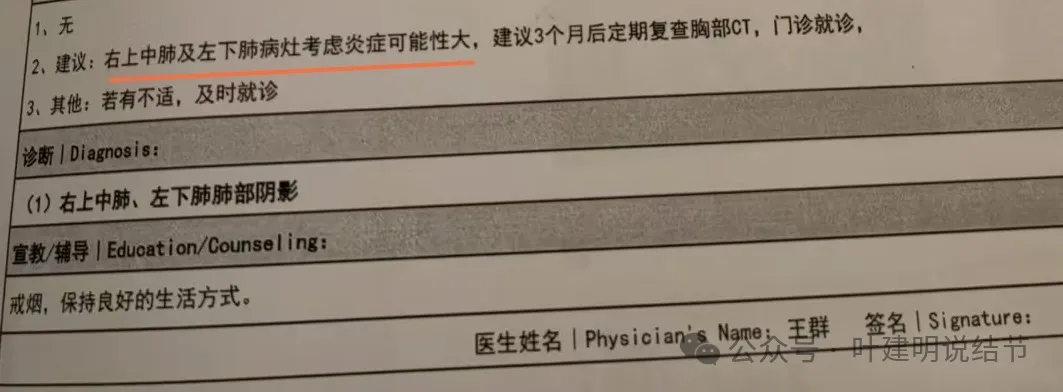

这是10月复查后的报告,多发混杂GGO了。

上海中山医院王群教授意见是考虑炎症可能性大,建议3个月复查。